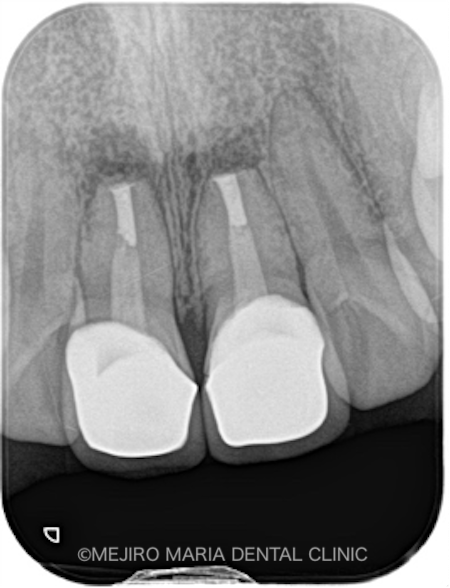

本症例の患者様は、2年前に交通事故で前歯を負傷しました。その際近隣の歯科医院で前歯2本を抜髄し、オールセラミッククラウンを装着されました。しかし、右上の1番はセラミック装着後すぐにろう孔が出現し同時に違和感を覚えるようになったため、治療を行った歯科医院に相談した結果、歯根端切除術を行ったとのことでした。

ところが歯根端切除術を施すも、根尖部の腫脹が改善されなかったため、当院に来院されました(1枚目写真の矢印)。

初診時にCT撮影を行い診査したところ、右上1番の根尖の骨は、根尖性歯周炎により喪失していました。また、左上1番の歯にも小さい病変(根尖性歯周炎)が確認されました(2枚目の写真)。

今回は下記の理由から、オールセラミッククラウンを除去せずに歯根端切除術を再び行う、という解決方法をご提案させていただきました。